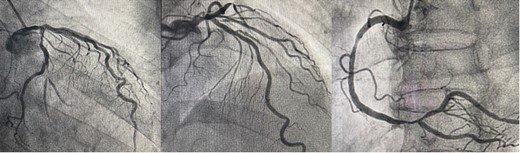

The patient was positioned by elevating in a 30° to 40° right lateral decubitus position to facilitate a widened intercostal space. The patient was intubated with a double-lumen endotracheal tube. A 10 cm left mini-thoracotomy was performed in the fourth intercostal space, with 1/3 of the incision medial to the mid-clavicular line. The ThoraTrak® MICS Retractor System (Medtronic Inc., MN, USA) was employed to achieve optimal access to the left chest and effectively visualize the internal mammary arteries. The LITA was harvested in a skeletonized fashion under direct vision, and the saphenous vein (SVG) was harvested from the right leg. To maintain the activated clotting time > 280 s, heparin (1 mg/kg) was administered after the LITA harvest. In this case, the Tentacles NEO (Sumitomo Bakeride, Akita, Japan) was used as a heart poisoner and cardiac stabilizer. We made four distal anastomoses (LITA-LAD, Aorta-SVG1-first diagonal, Y-composite SVG2-OM- posterolateral artery). When one of the suction cups attached to the apex of LV was detached, an epicardial hematoma was coming at the attachment site (Fig. 2). This bleeding point was repaired by continuous suture by 4–0 prolene with two big felt. After protamine was given, good hemostasis was achieved (Fig. 3).

The bleeding spot was repaired using a continuous suture with 4–0 prolene and two large felts. Following the administration of protamine, effective hemostasis was achieved.